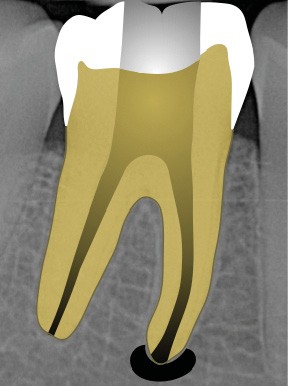

Perforation supra-osseuse (fig. 1)

Les perforations supra-crestales sont la plupart du temps iatrogéniques et surviennent lors de la réalisation de la cavité d’accès, ou de la recherche des entrées canalaires. Il s’agit généralement d’une communication avec un diamètre bien défini et aux contours nets. De ce fait, ce type de perforation est appelée « perforation à quatre parois ». Les perforations peuvent également être d’origine pathologique (résorption cervicale externe, carie active).